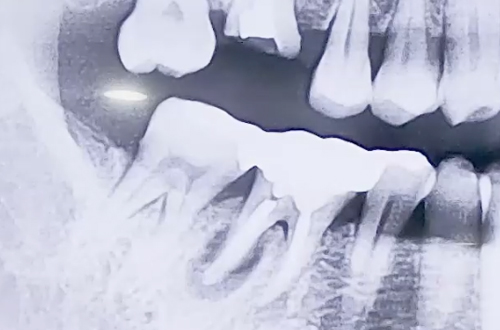

BEFORE

오른쪽 아래 큰 어금니가 굉장히 심하게 붓고 통증이 있는 상태로

내원해 주신 환자분의 사례로, 해당 치아의 흔들림이 심했습니다.

엑스레이를 찍어보니 어금니의 뿌리 중 하나의 주변으로 염증이 생기면서

치아를 단단히 잡아주는 힘이 약해져 흔들리고 통증이 있던 것이었는데요.

때문에 발치 후 임플란트를 시행하기로 하였으나, 발치한 자리 가운데에

식립하기에는 염증으로 약해진 잇몸이 고민스러웠습니다.

때문에 염증을 피해 살짝 옆쪽으로 심고, 염증 부분은 치료한 뒤

뼈이식으로 정리해 드리는 방향으로 치료해 드렸습니다.